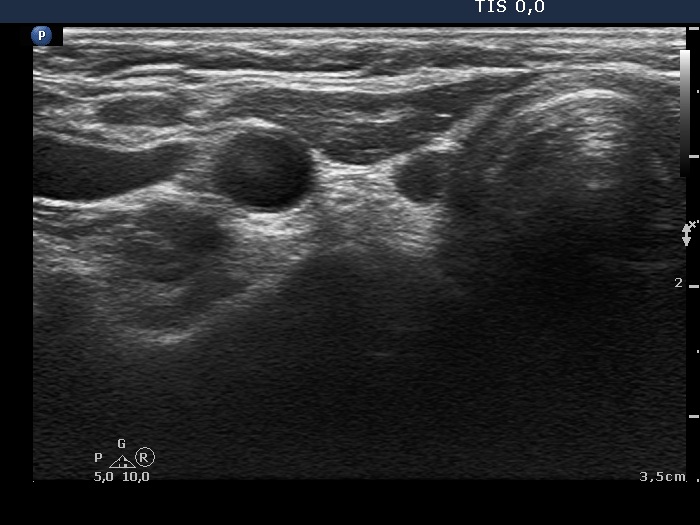

The operated thyroid - case 775 |

Clinical data: A 55-year-old woman was referred for follow-up examination. She underwent total thyroidectomy because of toxic multinodular goiter 7 years ago. She had no complaints.

Ultrasonography: There was no parenchyma according to the thyroid lobes.